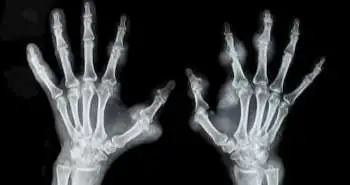

The current study aimed to estimate if there is a greater risk of adverse maternal and neonatal outcomes in pregnant women suffering from RA.

In pregnancy, several changes in the immune system take place which in turn affects the course of rheumatoid arthritis (RA). Hissay Aljary et al. evaluated in their cohort study that pregnant women are at a greater plausibility of adverse maternal and neonatal outcomes and they should also be made well-informed of these risks.